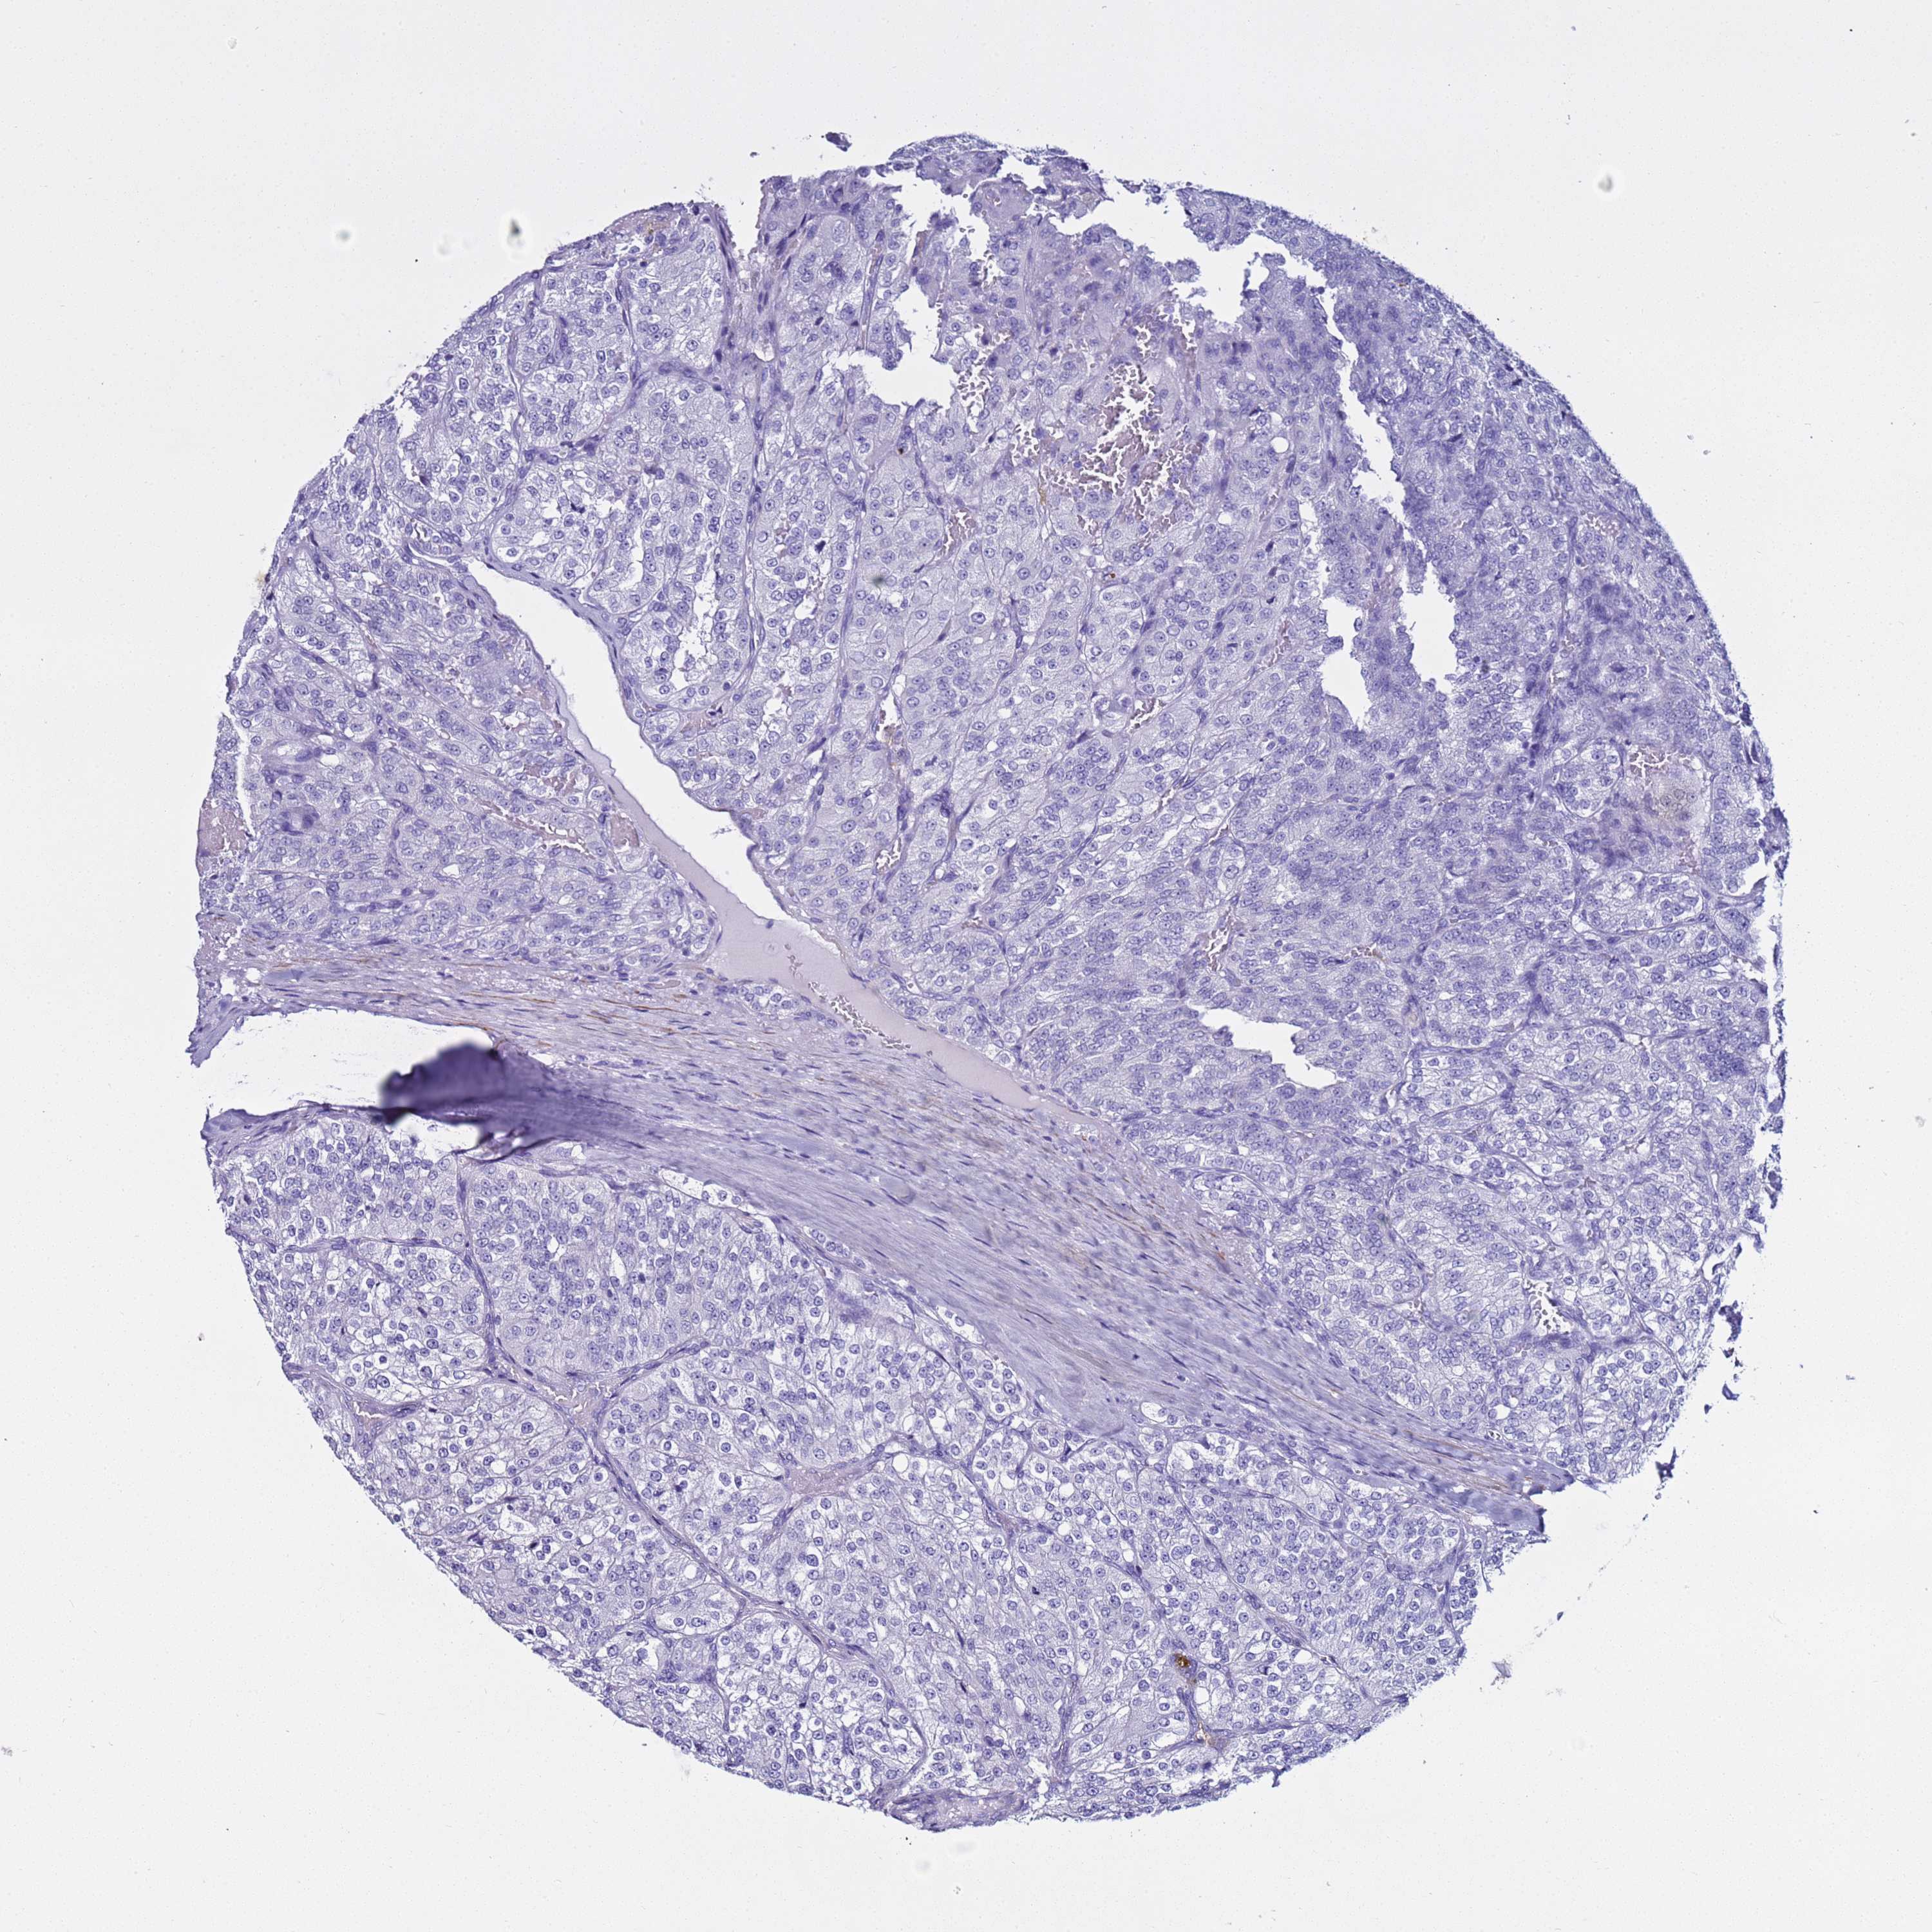

KIDNEY RENAL CLEAR CELL CARCINOMA (VALIDATION) - Interactive survival scatter ploti

The Survival Scatter plot shows the clinical status (i.e. dead or alive) for all individuals in the patient cohort, based on the same data that underlies the corresponding Kaplan-Meier plots. Patients that are alive at last time for follow-up are shown in blue and patients who have died during the study are shown in red.

The x-axis shows the expression levels (FPKM) of the investigated gene in the tumor tissue at the time of diagnosis. The y-axis shows the follow-up time after diagnosis (years). Both axes are complimented with kernel density curves demonstrating the data density over the axes. The top density plot shows the expression levels (FPKM) distribution among dead (red) and alive patients (blue). The right density plot shows the data density of the survived years of dead patients with high and low expression levels respectively, stratified using the cutoff indicated by the vertical dashed line through the Survival Scatter plot. This cutoff is automatically defined based on the FPKM cutoff that minimizes the p-score. The cutoff can be changed by dragging the vertical line or by entering a cutoff value in the square labeled "Current cut-off".

Under the Survival Scatter plot the p-score landscape (black curve; left axis) is shown together with dead median separation (red curve; right axis). Dead median separation is the difference in median mRNA expression between patients who have died with high and low expression, respectively. It is calculated as follows: median FPKM expression of dead patients with high expression - median FPKM expression of dead patients with low expression. This is intended to aid the user in visually exploring custom cutoffs and the associated p-scores and dead median separation.

Individual patient data is displayed and can be filtered by clicking on one or more of the category buttons on the top of the page. Categories describing expression level and patient information include: high, low, alive, dead, female, male and tumor stages. The scale of the x-axis can be toggled between linear and log-scale by clicking on the "x log" button. Mouse-over function shows TCGA ID, patient information and mRNA expression (FPKM) for each patient.

& Survival analysisi

Kaplan-Meier plots summarize results from analysis of correlation between mRNA expression level and patient survival. Patients were divided based on level of expression into one of the two groups "low" (under cut off) or "high" (over cut off). X-axis shows time for survival (years) and y-axis shows the probability of survival, where 1.0 corresponds to 100 percent.

LCMT1 is not prognostic in Kidney Renal Clear Cell Carcinoma (validation)

Best expression cut offi

Based on the FPKM value of each gene, patients were classified into two groups and association between prognosis (survival) and gene expression (FPKM) was examined. The best expression cut-off refers the FPKM value that yields maximal difference with regard to survival between the two groups at the lowest log-rank P-value. Best expression cut-off was selected based on survival analysis .

When clicking on this number, the vertical dashed line indicating cut-off, the interactive survival plot, and the Kaplan-Meier curve will be adjusted to show results based on the best expression cut-off.

: 28.51

TCGA RNA samplesi

RNA-seq data is reported as average FPKM (number Fragments Per Kilobase of exon per Million reads), generated by the The Cancer Genome Atlas (TCGA) .

Normal distribution across the dataset is visualized with box plots, shown as median and 25th and 75th percentiles. Points are displayed as outliers if they are above or below 1.5 times the interquartile range. FPKM values of the individual samples are presented next to the box plot.

Average pTPM 31.4

Number of samples 100